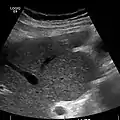

Imaging

Ultrasound is routinely used in the evaluation of cirrhosis. It may show a small and nodular liver in advanced cirrhosis along with increased echogenicity with irregular appearing areas. Other liver findings suggestive of cirrhosis in imaging are an enlarged caudate lobe, widening of the fissures and enlargement of the spleen. An enlarged spleen (splenomegaly), which normally measures less than 11–12 cm in adults, can be seen and may suggest underlying portal hypertension. Ultrasound may also screen for hepatocellular carcinoma, portal hypertension, and Budd-Chiari syndrome (by assessing flow in the hepatic vein). An increased portal vein pulsatility is an indicator of cirrhosis, but may also be caused by an increased right atrial pressure.[33] Portal vein pulsatility can be quantified by pulsatility indices (PI), where an index above a certain cutoff indicates pathology:

Liver cirrhosis with ascites

caudate lobe hypertrophy in ultrasound due to cirrhosis